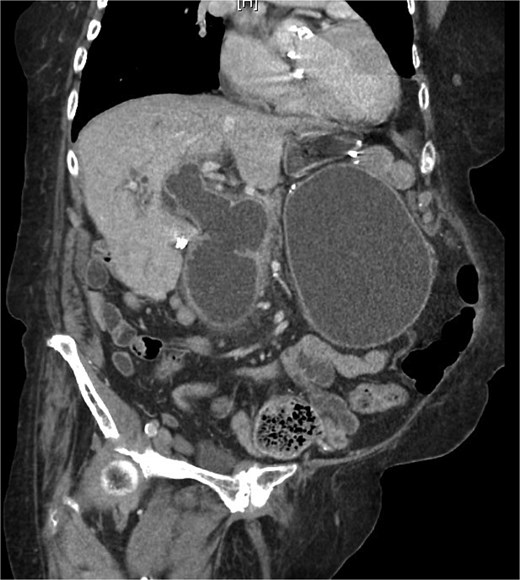

On examination, she was afebrile and hemodynamically stable. Her abdomen was mildly distended with epigastric tenderness and firmness. Laboratory workup revealed moderate leukocytosis (13.3 × 109/l), elevated lipase (288 U/l), and normal total bilirubin (0.8 mg/dl). Contrast-enhanced computed tomography (CT) demonstrated distention of the remnant stomach, duodenum (biliopancreatic limb), CBD, and intrahepatic ducts. A 9.0 × 3.4 cm heterogeneous mass was visualized in the duodenum, consistent with an obstructing gallstone (Figs 1–3).

CT demonstrating gallstone within the common bile duct 1 month prior to this admission.

(a and b) CT demonstrating gallstone in D3-D4 with BPD limb obstruction.